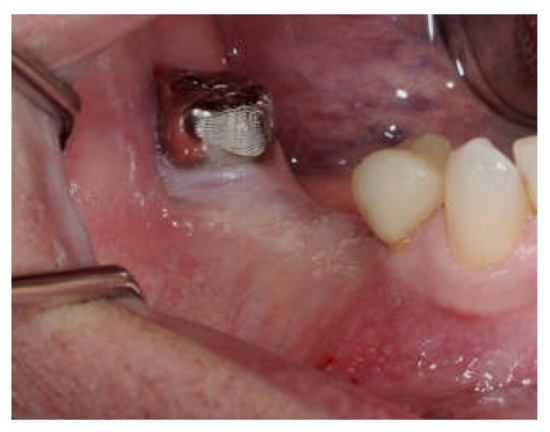

Clinical and CBCT aspects of patient from the test group, describing the stages of S-GBR technique and implant-prosthetic stage, are presented in Figure 1, Figure 2, Figure 3, Figure 4, Figure 5, Figure 6, Figure 7, Figure 8, Figure 9, Figure 10 and Figure 11. CBCT exam allows the evaluation of the horizontal alveolar bone defect and the position of the mandibular alveolar nerf (Figure 1A,B). Figure 1C,D show cross-sectional CBCT aspects of the implant sites. Figure 2 shows the narrowed mandibular alveolar bone with horizontal resorption. Figure 3 shows the exposed buccal surface of the alveolar ridge with severe horizontal resorption, after flap opening. The inserted implants (4.5 mm diameter, 11.5 mm length) and osteosynthesis screws (45° from the occlusal plan) are shown in Figure 4A. The placement of graft (autologous bone and xenograft) and collagen membrane is shown in Figure 4B. Figure 5A shows tension-free sutures, due to periosteal incisions alveolar ridge. Figure 5B shows clinical aspect at 7 months after surgery, with gingival tissue adherent on the reconstructed alveolar ridge. Figure 6 shows OPG aspect at follow-up of 7 months, with osseointegration of the dental implants. Figure 7A shows clinical aspect before osteosynthesis screws removal. Figure 7B shows clinical aspect after osteosynthesis screws removal. Figure 8A shows healthy peri-implant soft tissues. Figure 8B shows repositioning key for perfect position of abutments. Figure 10A,B show clinical aspects of implant-supported prosthetic restoration. Figure 11A,B show CBCT aspects of Osseo integrated dental implants at 24 months follow-up.

Figure 9.

(A,B) Post-operative clinical aspects 3 weeks after second stage surgery. (A) Healthy peri-implant soft tissues (B) The repositioning key of abutments.